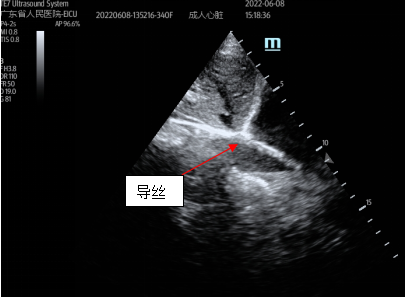

接受治疗的患者被诊断为“重症肺炎、心源性休克、ARDS、干燥综合征、肺间质病变”,由普通病房转入EICU时,已由江稳强主任带领的急诊ECMO团队行VA-ECMO支持,患者循环功能稳定后转为VV-ECMO, ARDS缓解后双肺间质性病变仍无明显改善,经院内MDT讨论后认为:患者需长期ECMO支持等待肺移植。EICU团队与体外循环团队讨论后认为:切换为单管双腔ECMO插管可有效降低院感发生率,为患者提供更舒适的救治方式,并尽早在清醒状态下进行康复治疗。经家属同意,立即为患者进行了经胸超声引导下双腔颈静脉插管,继续VV-ECMO支持治疗。

双腔插管置管成功